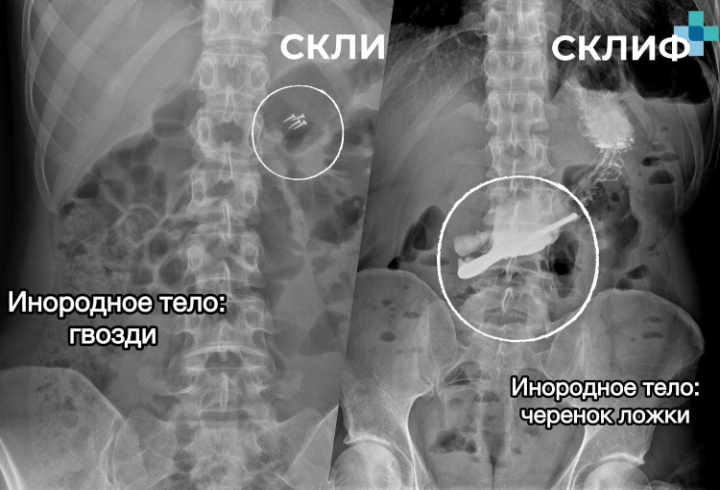

По данным института, за год медикам приходилось удалять беспроводные наушники, зубные коронки, абрикосовые косточки, черенки ложек, украшения и даже гвозди. Чаще всего инородные предметы пациенты проглатывали случайно, в том числе во время проведения ремонтных работ.

В Склифосовском отметили, что подобные случаи, несмотря на кажущуюся курьезность, представляют серьезную опасность. Ежегодно в институт поступают десятки пациентов с инородными телами, которым требуется экстренная медицинская помощь и, в отдельных случаях, длительное восстановление.

Фото: Телеграм-канал «Склиф»